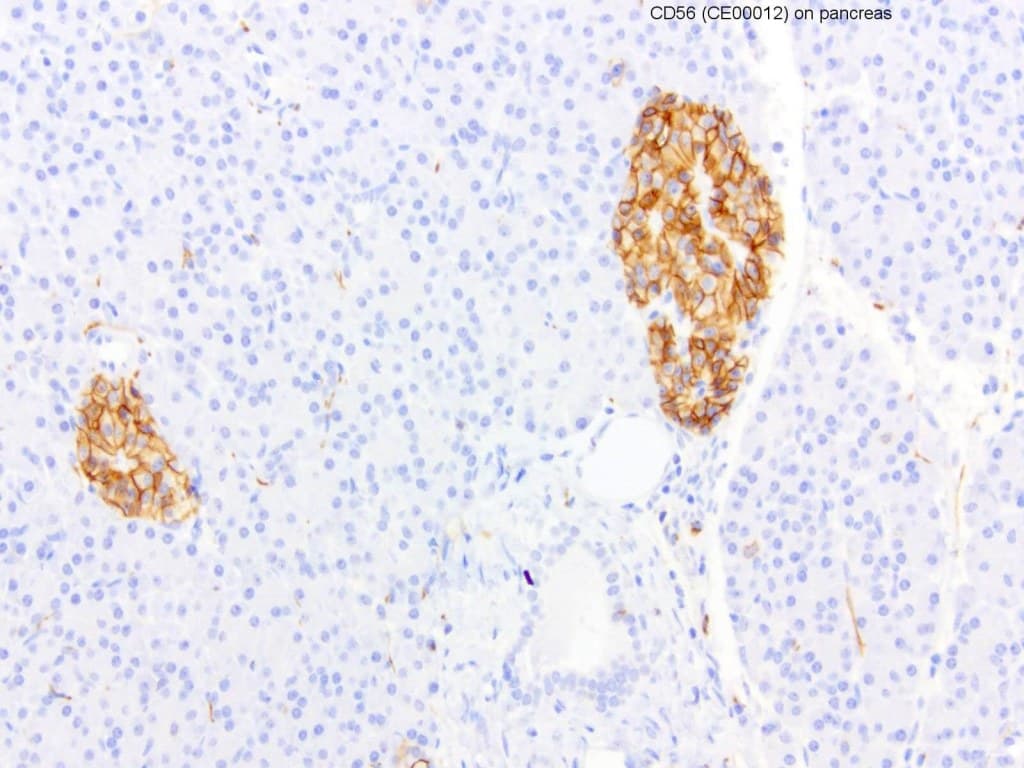

Les anticorps Anti-CD56 (molécule d’adhésion cellulaire neuronale, NCAM) CE/IVD pour immunohistochimie (IHC) permettent une détection fiable de CD56 dans les tissus fixés au formol et inclus en paraffine (FFPE), facilitant un immunophénotypage précis en hématopathologie. CD56 est une glycoprotéine transmembranaire de la superfamille des immunoglobulines, avec plusieurs isoformes (NCAM 120, NCAM 140, NCAM 180) qui diffèrent par la longueur de leur domaine intracellulaire et leur distribution tissulaire. Elle est principalement exprimée par les cellules NK et certaines sous-populations de lymphocytes T, avec également une expression observée dans certains types cellulaires néoplasiques.

- Expression dans le système immunitaire : Son expression élevée sur les cellules NK et certains lymphocytes T activés reflète des fonctions cytotoxiques et de surveillance immunitaire.

- Lymphomes à cellules NK et néoplasmes associés : L’IHC CD56 constitue un marqueur clé pour une classification précise.

- Haute spécificité : Les anticorps monoclonaux garantissent une détection reproductible avec une réactivité croisée minimale.

- Intégration dans des panels : Complètent les panels d’immunophénotypage pour améliorer la précision diagnostique.